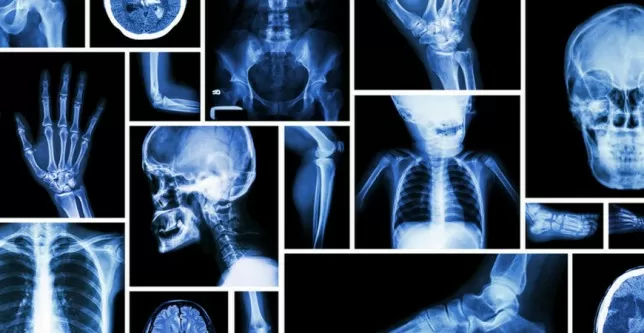

World Radiography Day 2021: हर साल 08 नवंबर को विश्व स्तर पर विश्व रेडियोग्राफी दिवस (International Day of Radiography) मनाया जाता है. यह दिन रेडियोग्राफी के उस मूल्य के बारे में जागरूकता को बढ़ावा देने हेतु मनाया जाता है, जो सुरक्षित रोगी देखभाल में योगदान देता है, और स्वास्थ्य देखभाल की निरंतरता में अहम भूमिका रेडियोलॉजिस्ट और रेडियोग्राफर की सार्वजनिक समझ में निरंतर सुधार करता है.

इस दिन लोगों के बीच  रेडियोग्राफी के बारे में जागरूकता बढ़ाया जाता है. रेडियोलॉजिस्ट और रेडियोलॉजिकल टेक्नोलॉजिस्ट स्वास्थ्य सेवा में एक अहम भूमिका निभाता है. यह रोगियों की देखभाल करने में सहायता करता है. एक्स-रे लोगों के स्वास्थ्य संबंधी समस्याओं को खोजने में सहायता करती हैं.

रेडियोलॉजिकल सिस्टम ज्यादातर मरीजों में बीमारियों का पता लगाने हेतु उपयोग किया जाता है. रेडियोलॉजी एक्स-रे, एमआरआई स्कैनिंग उपकरण और अल्ट्रासाउंड उपकरणों के लिए एक महत्वपूर्ण आवश्यकता है. रेडियोलॉजी इसलिए लोगों के लिए आवश्यक है, क्योंकि इससे लोगों की अंदरूनी समस्या के बारे में जान सकते हैं. रेडियोलॉजिकल तकनीक केवल चिकित्सा क्षेत्र के बारे में नहीं हैं, वे चिकित्सा, प्रौद्योगिकी, वैज्ञानिक सिद्धांतों और कलात्मक कौशल के क्षेत्रों का एक सुंदर संयोजन हैं.